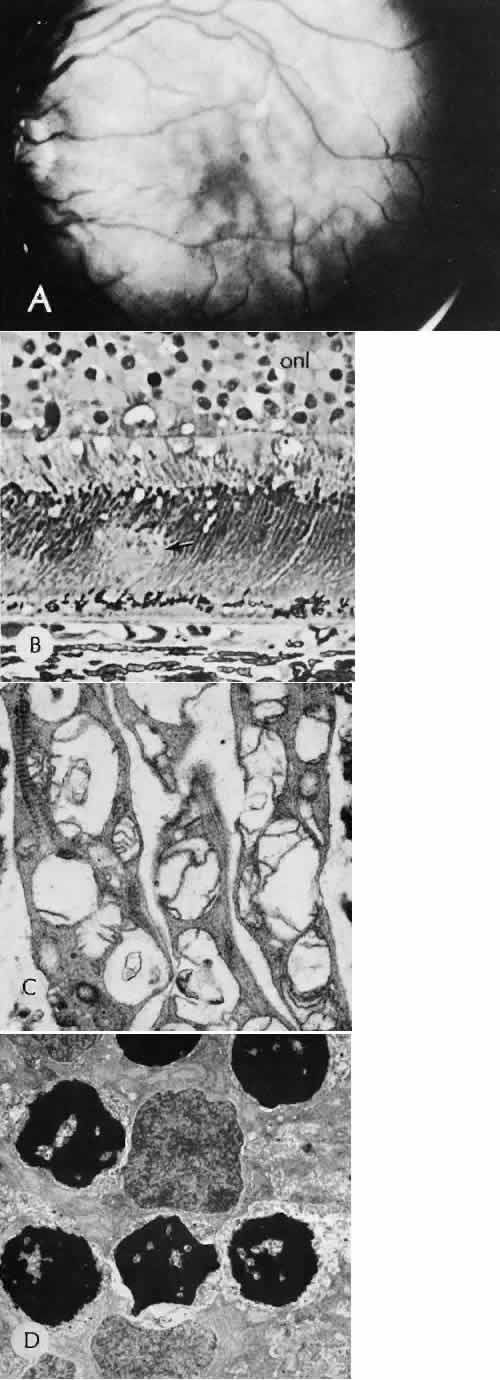

study of the evolution of retinal lesions in the rhesus monkey. American Journal of Ophthalmology 75(4):610–626, 1973. 44. Tso MO, Wallow IH, Elgin S: Experimental photocoagulation of the human retina. Archives of Ophthalmology 95(6):1035–1040, 1977. 45. Wallow IH, Tso MO, Elgin S: Experimental photocoagulation of the human retina. II. Electron microscopic

study. Archives of Ophthalmology 95(6):1041–1050, 1977. 46. Yoon YH, Marmor MF: Rapid enhancement of retinal adhesion by laser photocoagulation. Ophthalmology 95(10):1385–1388, 1988. 47. Miller B, et al: Effect of the vitreous on retinal wound-healing. Graefes Archive for Clinical & Experimental Ophthalmology 224(6):576–579, 1986. 48. Yamana T et al: The process of closure of experimental retinal holes in rabbit eyes. Gaefes Archive for Clinical & Experimental Ophthalmology 238(1):81–87, 2000. 49. Ozaki S et al: Influence of the sensory retina on healing of the rabbit retinal pigment

epithelium. Current Eye Research 16(4):349–358, 1997. 50. Perry DD, Reddick RL, Risco JM: Choroidal microvascular repair after argon laser photocoagulation. Ultrastructural

of the reattached retina. American Journal of Ophthalmology 67(1):117–130, 1969. 86. Bettman JW Jr: Pathology of complications of intraocular surgery. American Journal of Ophthalmology 68(6):1037–1050, 1969. 87. Arango JL, Margo CE: Wound complications following cataract surgery. A case-control study. Archives of Ophthalmology 116(8):1021–1024, 1998. 88. Linebarger EJ et al: Phacoemulsification and modern cataract surgery. [Review] [404 refs]. Survey of Ophthalmology 44(2):123–147, 1999. 89. Pieramici D, Green WR, Stark WJ: Stripping of Descemet's membrane: a clinicopathologic correlation. [Review] [21 refs]. Ophthalmic Surgery 25(4):226–231, 1994. 90. Amaral CE, Palay DA: Technique for repair of Descemet membrane detachment. American Journal of Ophthalmology 127(1):88–90, 1999. 91. Benson WE et al: Late hyphema due to vascularization of the cataract wound. Annals of Ophthalmology 10(8):1109–1112, 1978. 92. Lumme P, Laatikainen LT: Risk factors for intraoperative and early postoperative complications in